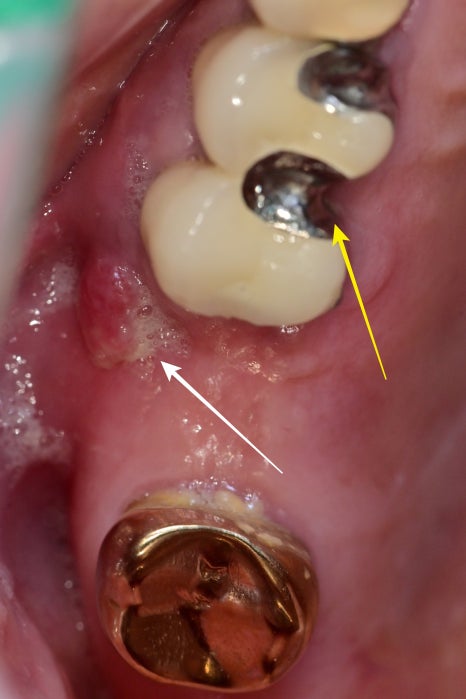

사진으로 보이는 노란색 화살표 부분이 틀니 고리가 거치되는 공간입니다.

치아 주변으로 틀니가 힘들 가해주게 되면 시간이 지나면 치아도 흔들리고

수명에 영향을 줄 수밖에 없습니다.

하얀색 화살표 부분을 보면 염증 때문에 잇몸이 과증식이 되어있었습니다.